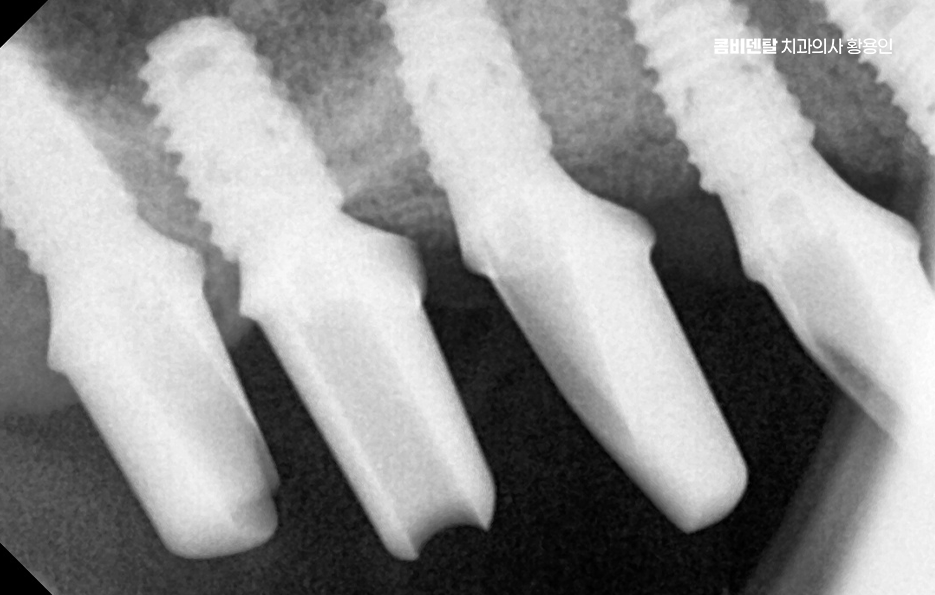

어금니 부위는 씹는 힘이 강한 만큼, 임플란트에 전달되는 하중도 커서 단순히 임플란트를 심는 것뿐 아니라, 그 힘을 어떻게 분산시킬 것인지에 대한 계획이 중요한데 임플란트의 위치, 각도, 크기, 그리고 위에 올라가는 보철물의 형태까지 함께 고려되어야 하며 이 과정이 충분히 고려되지 않으면, 임플란트 자체는 괜찮아 보여도 시간이 지나면서 주변 뼈에 무리가 가거나, 보철물이 깨지는 문제가 생길 수 있어요.

뼈이식이 필요하다고 해서 모두 같은 방식으로 진행되는 것은 아니며 부족한 뼈의 양과 위치에 따라 치료 방법과 범위는 달라지며 소량의 보완만 필요한 경우에는 임플란트를 심으면서 동시에 진행되기도 하고, 뼈 상태가 많이 부족한 경우에는 일정 기간 뼈가 자리 잡을 시간을 갖고 나서 임플란트를 진행하기도 해서 이 과정은 개인 상태에 따라 달라지기 때문에, 획일적으로 생각하기보다는 맞춤 계획으로 접근해야 하는 거예요